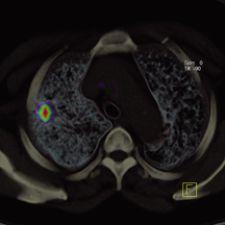

PET/CT in molecular imaging takes a 'photograph' of biological targets or pathways in the body for 'personalized medicine.' Photo courtesy of Siemens.

Over the next 10 years, the hybrid PET/CT modality is expected to surpass dedicated PET devices in terms of adoption, as the combined functional and anatomical information produced by the hybrid has proven increasingly beneficial in oncology and cardiology. PET/CT will also play an important role in the future of molecular imaging, which aims to “photograph” biological targets or pathways in the body for “personalized medicine,” which will eventually provide patient-specific information that allows clinicians to tailor the treatment of disease. These developments have charged the leading PET/CT manufacturers, GE Healthcare, Siemens, Hitachi and Philips, with enhancing image quality in the hybrid – particularly in PET. What is intriguing is that each manufacturer is approaching this challenge in its own way.